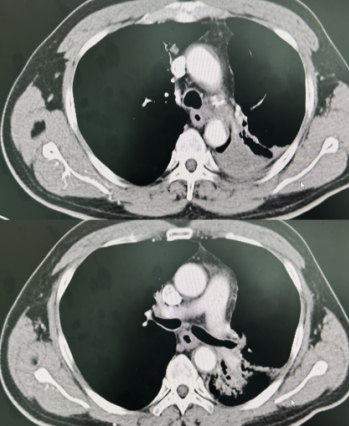

自2024年7月起,由卢冰教授率领贵州医科大学附属医院、附属肿瘤医院胸部肿瘤科团队和放射物理师团队率先开展SFRT的临床应用,至今已完成几十例患者的临床治疗。第1例应用SFRT治疗的患者由卢冰教授带领李青松副主任医师、胡银祥高级工程师完成。对一例LA-NSCLC患者在同期放化疗联合免疫维持治疗的标准治疗模式中,放疗采用SFRT,疗程结束时肿瘤明显缩小,定期随访发现肿瘤完全消失(图示),取得了远超常规放疗的临床效果,而且无明显的放疗并发症,病人生活质量满意,可自行驾车外出游玩。

放疗结束后

1个月CT影像

7个月CT影像